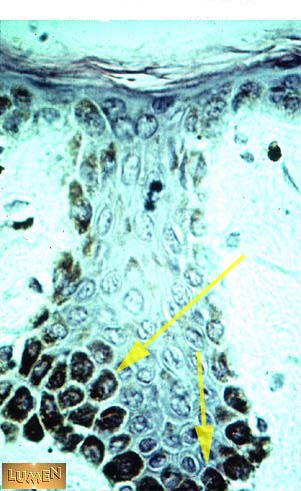

These cells are filled with what dark substance?

Melanin